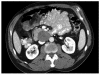

Isolated extragonadal germ cell tumors can be primary in nature or metastatic from a burned out testicular cancer. Accurate diagnosis is critical as appropriate therapy can be highly curative. We present the case of an isolated extragonadal germ cell tumor in the retroperitoneum diagnosed by endoscopic ultrasound-guided fine needle aspiration. This case underscores the importance of considering germ cell tumors in the differential diagnosis of an unexplained retroperitoneal mass, particularly since immunophenotypic staining may be necessary to establish the diagnosis.